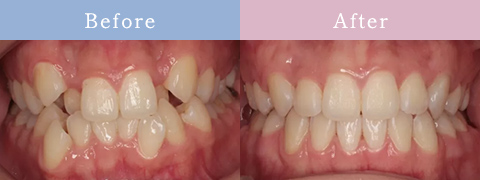

CASE症例

歯並びだけじゃない「お顔全体のバランスまで追求」

歯並びが原因でお顔立ちに

影響を与えている場合は

矯正治療で改善できます